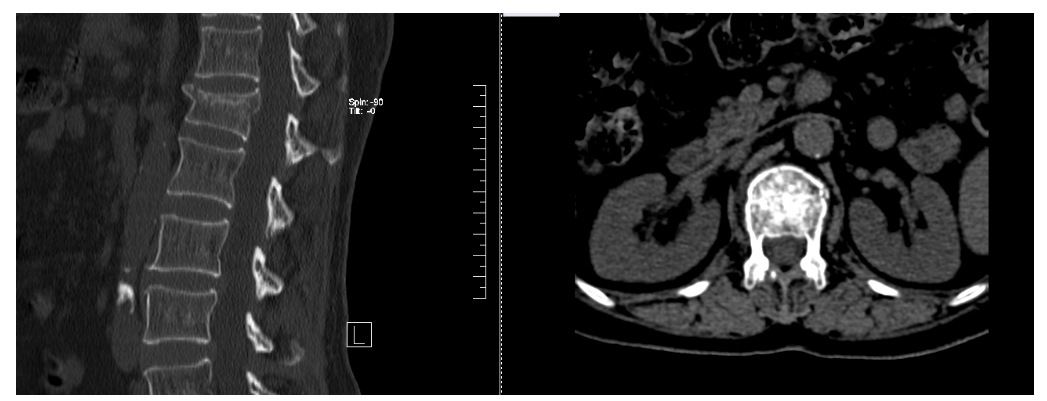

主诉:腰部疼痛3小时

现病史:患者3小时前不慎摔倒后出现腰部疼痛,活动时明显,休息时轻微缓解。不伴下肢麻木等,至当地医院诊治,查腰椎正侧位X线:L1椎体压缩性改变,考虑骨折。今日为求诊治,来我院椎间盘科,以“骨质疏松症,L1椎体骨质疏松性压缩骨折,冠心病”为诊断收住我科。发病以来,饮食正常,睡眠一般,体力正常,大小便正常。